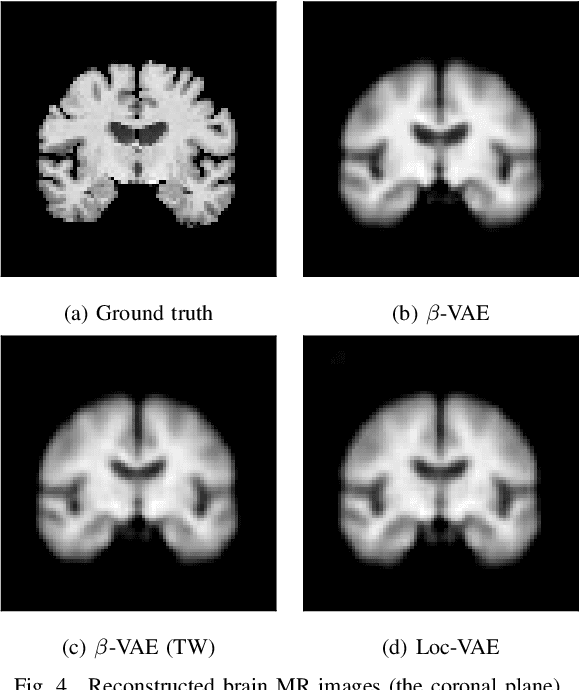

Abstract:Content-based image retrieval (CBIR) systems are an emerging technology that supports reading and interpreting medical images. Since 3D brain MR images are high dimensional, dimensionality reduction is necessary for CBIR using machine learning techniques. In addition, for a reliable CBIR system, each dimension in the resulting low-dimensional representation must be associated with a neurologically interpretable region. We propose a localized variational autoencoder (Loc-VAE) that provides neuroanatomically interpretable low-dimensional representation from 3D brain MR images for clinical CBIR. Loc-VAE is based on $\beta$-VAE with the additional constraint that each dimension of the low-dimensional representation corresponds to a local region of the brain. The proposed Loc-VAE is capable of acquiring representation that preserves disease features and is highly localized, even under high-dimensional compression ratios (4096:1). The low-dimensional representation obtained by Loc-VAE improved the locality measure of each dimension by 4.61 points compared to naive $\beta$-VAE, while maintaining comparable brain reconstruction capability and information about the diagnosis of Alzheimer's disease.